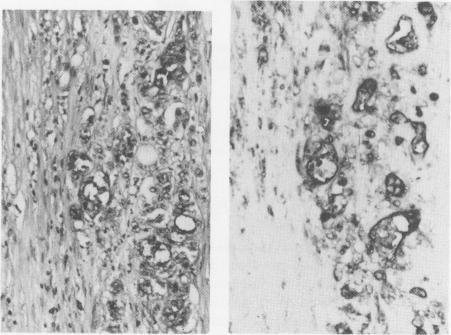

The expression of the gastrointestinal cancer associated antigen CA 19-9, defined by the monoclonal antibody 1116 NS 19-9, was studied by immunoperoxidase staining in routine formalin-fixed, paraffin-embedded tissue sections from normal pancreata, pancreata with pancreatitis and from benign and malignant pancreatic neoplasms. The formalin-fixed specimens were treated with pepsin, which enhanced the staining intensity. Eighty-five per cent of well to moderately differentiated adenocarcinomas were positive. The staining was most intense in the apical border of cells lining the lumina of malignant glands, and in mucus inside the lumina, but cytoplasmic staining was also seen. In poorly differentiated adenocarcinomas the number of positive cells was smaller and in anaplastic carcinomas only occasional cells were stained. All mucinous cystadenomas and cystadenocarcinomas stained intensely, whereas serous cystadenomas, and all benign and malignant islet cell tumours were negative. Ducts in chronic pancreatitis and in normal pancreata were positive in 96% and 79%, respectively, but the staining was focal and usually weaker than in carcinomas. In acute pancreatitis (92% positive) the staining was more intense, and the CA 19-9 expression was seen predominantly in small terminal ducts and in centroacinar cells. There was an apparent correlation between the degree of differentiation of the ductal adenocarcinomas and the expression of CA 19-9, whereas the correlation between tissue expression and serum levels of CA 19-9 was poor.

采用免疫过氧化物酶染色法,以单克隆抗体1116 NS 19-9为标记,对正常胰腺、胰腺炎胰腺以及良恶性胰腺肿瘤的常规福尔马林固定、石蜡包埋组织切片进行研究,观察胃肠道癌相关抗原CA 19-9的表达情况。福尔马林固定标本经胃蛋白酶处理后,染色强度增强。85%的高分化至中分化腺癌呈阳性。染色在恶性腺管腔面细胞的顶端边界及管腔内黏液中最为强烈,但也可见胞质染色。在低分化腺癌中,阳性细胞数量较少,而在未分化癌中仅有偶尔的细胞被染色。所有黏液性囊腺瘤和囊腺癌均呈强染色,而浆液性囊腺瘤以及所有良恶性胰岛细胞瘤均为阴性。慢性胰腺炎和正常胰腺中的导管阳性率分别为96%和79%,但染色呈局灶性,通常比癌组织中的染色弱。在急性胰腺炎中(92%阳性),染色更强,且CA 19-9表达主要见于小终末导管和中央腺泡细胞。导管腺癌的分化程度与CA 19-9的表达之间存在明显相关性,而组织表达与CA 19-9血清水平之间的相关性较差。